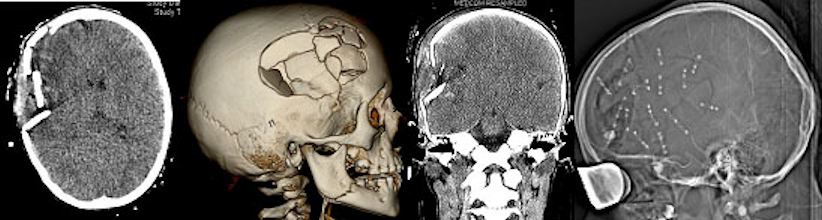

Trauma

Rekonstruktive Indikationen bei Schädeltraumen sind häufig. Immerhin ca. 83.400 Kinder unter 15 Jahren werden jedes Jahr im Krankenhaus behandelt, davon haben 80% ein leichtes, 20% jedoch ein schweres SHT. Davon erleiden etwa 4% eine Schädelfraktur. Kommt es zu einer Impressionsfraktur muss manchmal eine Hebung oder Rekonstruktion der Kalotte erfolgen. In extremen Fällen (Abbildung 6 [Abb. 6]) benötigen auch einmal solche verletzten Kinder eine umfangreiche Rekonstruktion der Integrität ihrer Kalotte, häufig auch im Bereich der Frontobasis. Zur Rekonstruktion fehlender oder aus Gründen der Verletzung zu verwerfender Knochenanteile stehen dabei bei Kindern Split bone-Techniken zur Verfügung. Dabei wird die Kalotte in Lamina interna und externa getrennt und steht somit als autologes Präparat zur Verfügung (Abbildung 7 [Abb. 7]). Vor allem beim kindlichen, wachsenden Schädel bietet dies Vorteile. Alternativ kommen heute auch Fremdmaterialien, Titanmesh aber auch Custome bone-Verfahren zum Einsatz.

Abbildung 6: Offenes SHT mit Impressionsfraktur nach Misshandlung mit Hammerschlag, primäre Rekonstruktion und gutes neurologisches Outcome bei 10-jährigem Mädchen